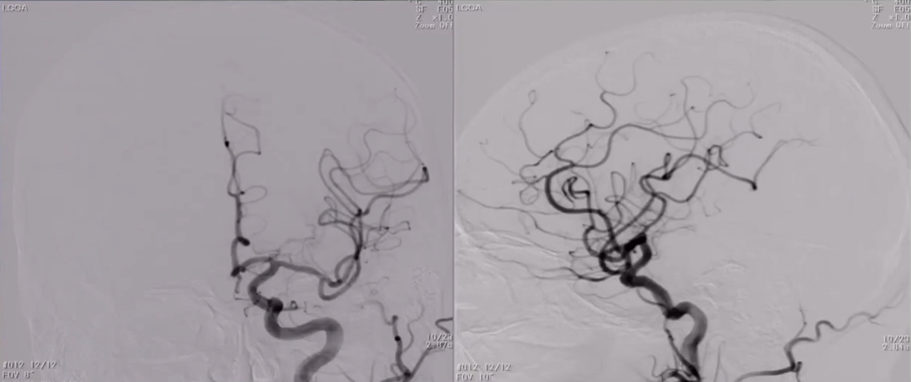

DSA:双侧颈内动脉起始部重度狭窄;前交通及双侧后交通未开放。

8F Fluxcap®球囊导引导管在5FMPA多功能125cm导管同轴辅助下送至右侧颈总动脉,微导丝送至C4段,沿微导丝送入6mm保护伞至C2段平直段,手推造影显示保护伞打开良好。

沿保护伞导丝送入4.0mm×30mm球囊,充盈球囊导引导管的球囊阻断血流,于狭窄段定位后命名压扩张球囊,泄球囊时在球囊导引导管的体外端予以负压回抽血液,取出一2mm血栓。经Fluxcap®球囊导引导管输送7.0-10.0mm×40mm自膨支架(Protégé RX)至狭窄段确认位置后释放。应用125cm多功能导管回收保护伞,多功能导管体外端予以负压回抽血液,保护伞内有血栓。

造影可见残余狭窄10%左右,颅内各分支血管通畅。